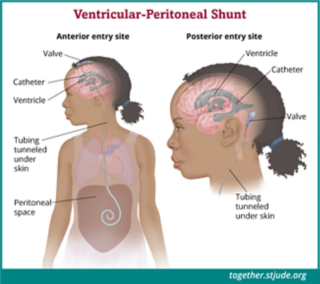

X Ray Multiple Part Of Child S Body Multiple Disease Stroke Brain Tumor Rheumatoid Arthritis Sinusitis Gouty Arthritis Etc Skull Chest Lung Heart Spine Arm Hand